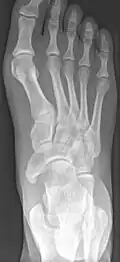

Radiological images

Cornuate navicular bone -